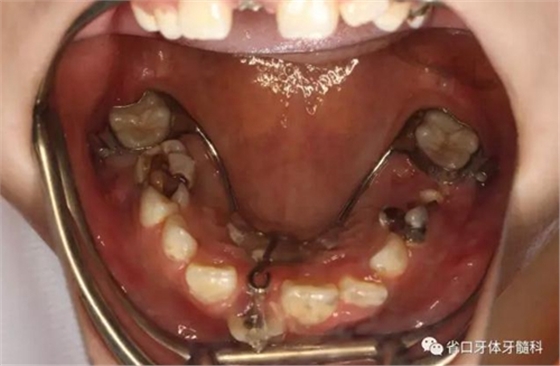

檢查:替牙列,12、21已萌出,11、22未萌,12、21間隙約5mm,右上前牙區(qū)前庭溝處見黏膜隆起,11牙冠未破齦。

口內(nèi)情況:牙合 面觀